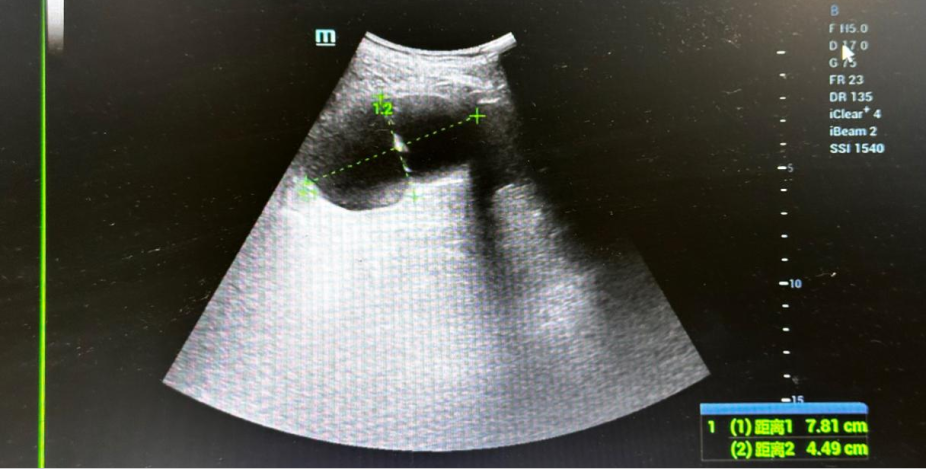

临床医师在彩超医师的配合下行肾囊肿穿刺引流,生理盐水冲洗,接着开始聚桂醇硬化治疗,屏幕显示肾囊肿逐渐缩小。

手术时引流前超声图片